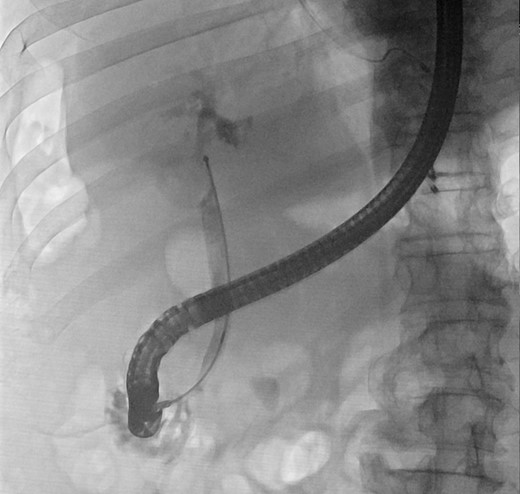

We report a case of a 67-year-old man, who presented with fever, chills and jaundice to a local district hospital. He had a temperature of 39°C and new-onset atrial fibrillation. Examination of the abdomen showed no peritoneal signs. Blood biochemistry demonstrated leukocytosis and abnormal liver function tests: bilirubin 75 μmol/L, alkaline phosphatase 1018 unit/L, alanine transaminase 177 unit/L. Ultrasound scan showed a 3 cm gallstone without common bile duct dilatation. However, computed tomography of abdomen revealed a gallstone eroding into the CHD, causing intrahepatic ductal dilatation (Fig. 1). The diagnosis of type II Mirizzi syndrome was confirmed by endoscopic retrograde cholangiopancreatography (ERCP), where cholangiogram demonstrated a gallstone fistulating into the CHD (Fig. 2). Biliary stent was inserted and intravenous antibiotics were given to tie over this acute episode of cholangitis.

Cholangiogram demonstrating filling defects at the common hepatic duct.